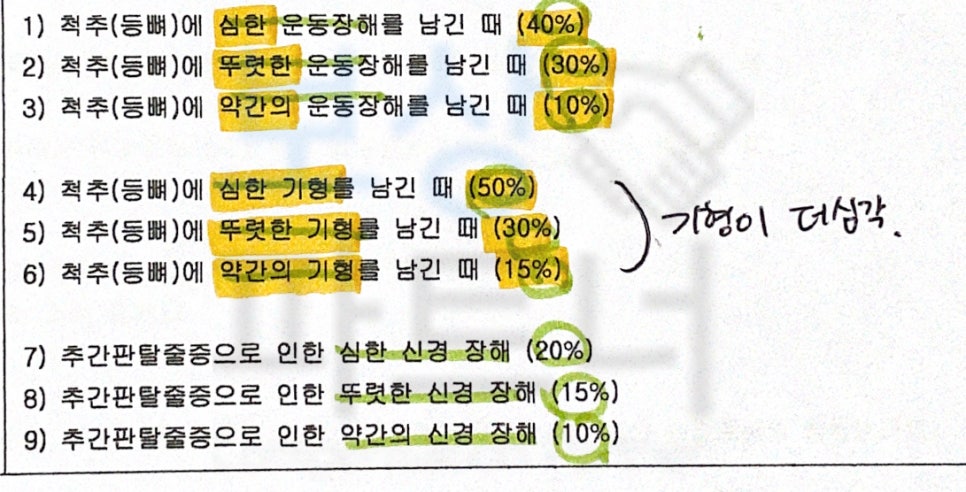

생명보험의 경우 무재해상해특약 이라는 항목을 통해 후유장해 보상이 가능합니다. 손해보험의 경우 상해후유장해 3% ~ 80% 미만 혹은 일반상해후유장해 확인해보시길 바랍니다. 또 주계약이나 기본계약에서 상해후유장해 보상 내용이 포함되어 있는지 면밀한 확인이 필요합니다.

의료 전문의로부터 장해 평가를 받고 평가된 진단서를 발급받아 청구하게 됩니다. 하지만 장해를 평가하는 시작부터 자신의 장해에 대해 부적합한 평가로 인해 올바른 보상을 받지 못하는 분들이 많으십니다.

보험사의 자체의료자문을 통해 환자가 발급받은 후유장해진단서가 과대평가되었다는 통보를 받기도 합니다.